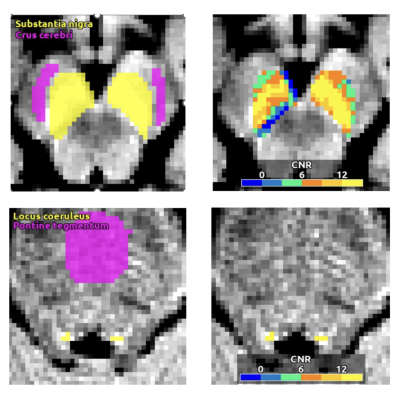

Terran Biosciences, Inc., a biotech platform company developing therapeutics and technologies for patients with neuropsychiatric illnesses, has received U.S. Food and Drug Administration (FDA) clearance to market NM-101, a cloud-based software platform to analyze neuromelanin-sensitive MRI scans. Image courtesy: Terran Biosciences, Inc.

“Now that we’re able to access measurements of neuromelanin-associated signal in both the substantia nigra and locus coeruleus,” added Dr. Cassidy, “it allows us to obtain potentially useful adjunctive information about many other diseases such as Alzheimer’s disease, and PTSD.”